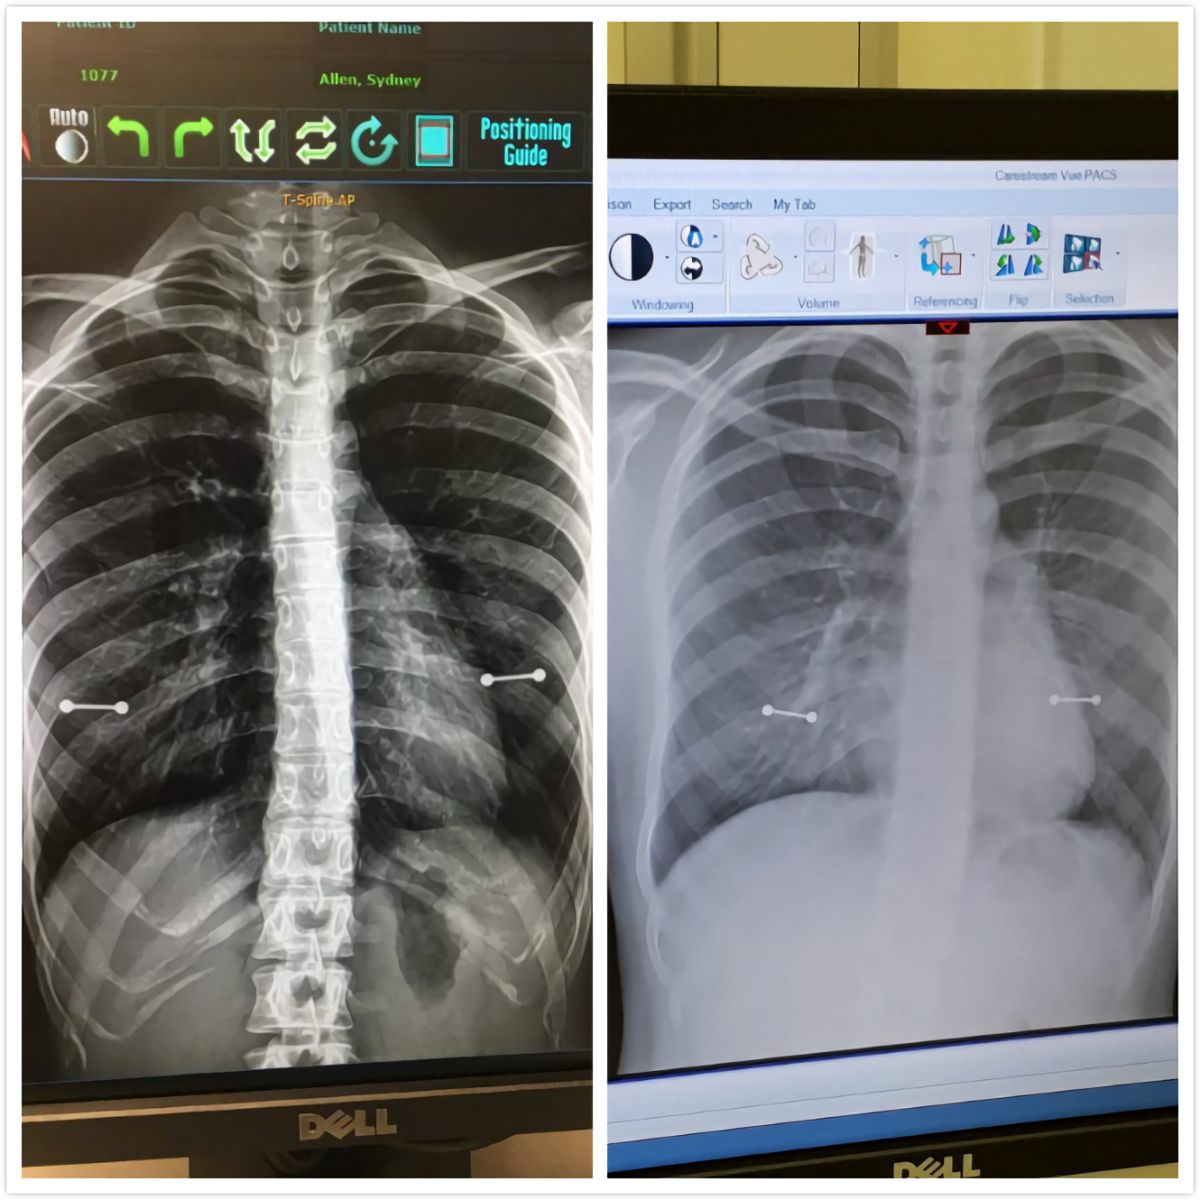

▲女子照 X 光胸前驚見 2 條金屬槓。(圖/翻攝自推特)

而 X 光照後會顯示體內金屬,艾倫沒在事前拿下乳環,結果 X 光照後顯示胸前有兩條「金屬槓」,當天媽媽也陪同艾倫檢查,眼見 2 條橫槓,媽媽立刻變臉,直說「看完醫生再討論這問題」,艾倫和醫生兩人則狂笑起來。